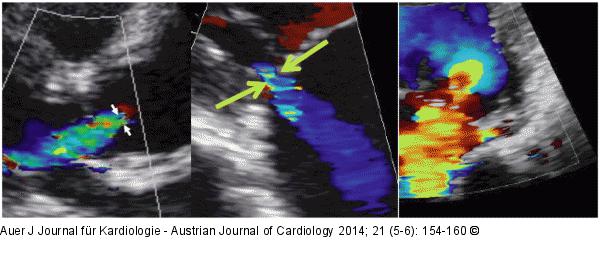

Abbildung 2: Herzklappeninsuffizienz